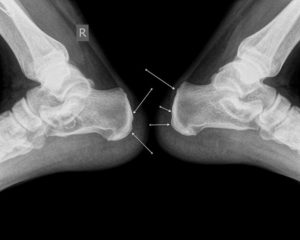

При исследования описанных нозологических форм обязательно сделать снимки в двух проекциях – прямая и боковая. Компьютерная томография назначается при наличии сомнений в реальном состоянии у пациента после травматического воздействия и заключением рентгенографии.

Для оценки смещения отломков и принятия решения травматологом относительно тактики лечения требуются снимки в двух проекциях. На боковой рентгенограмме четко визуализируется смещение кпереди или кзади. Прямой снимок показывает отклонение от продольной оси вправо или влево.

Смещение определяется по рентгенограммам, выполненным в двух разных проекциях (прямая, боковая). Фрагменты двигаются вдоль продольной, поперечной оси. Отломки между собой вклиниваются, возможно, захождение, расхождение.

По ширине прослеживается боковое смещение, по оси – угловое. Поворот одного отломка вокруг оси – ротация.